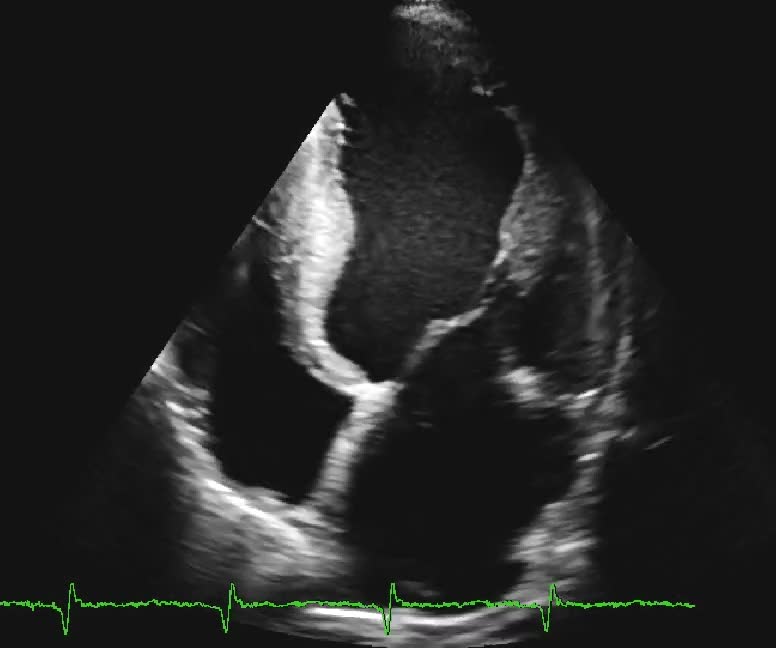

Cardiomiopatia aritmogena

Autore:

Santo Dellegrottaglie

Oscar Gaddi